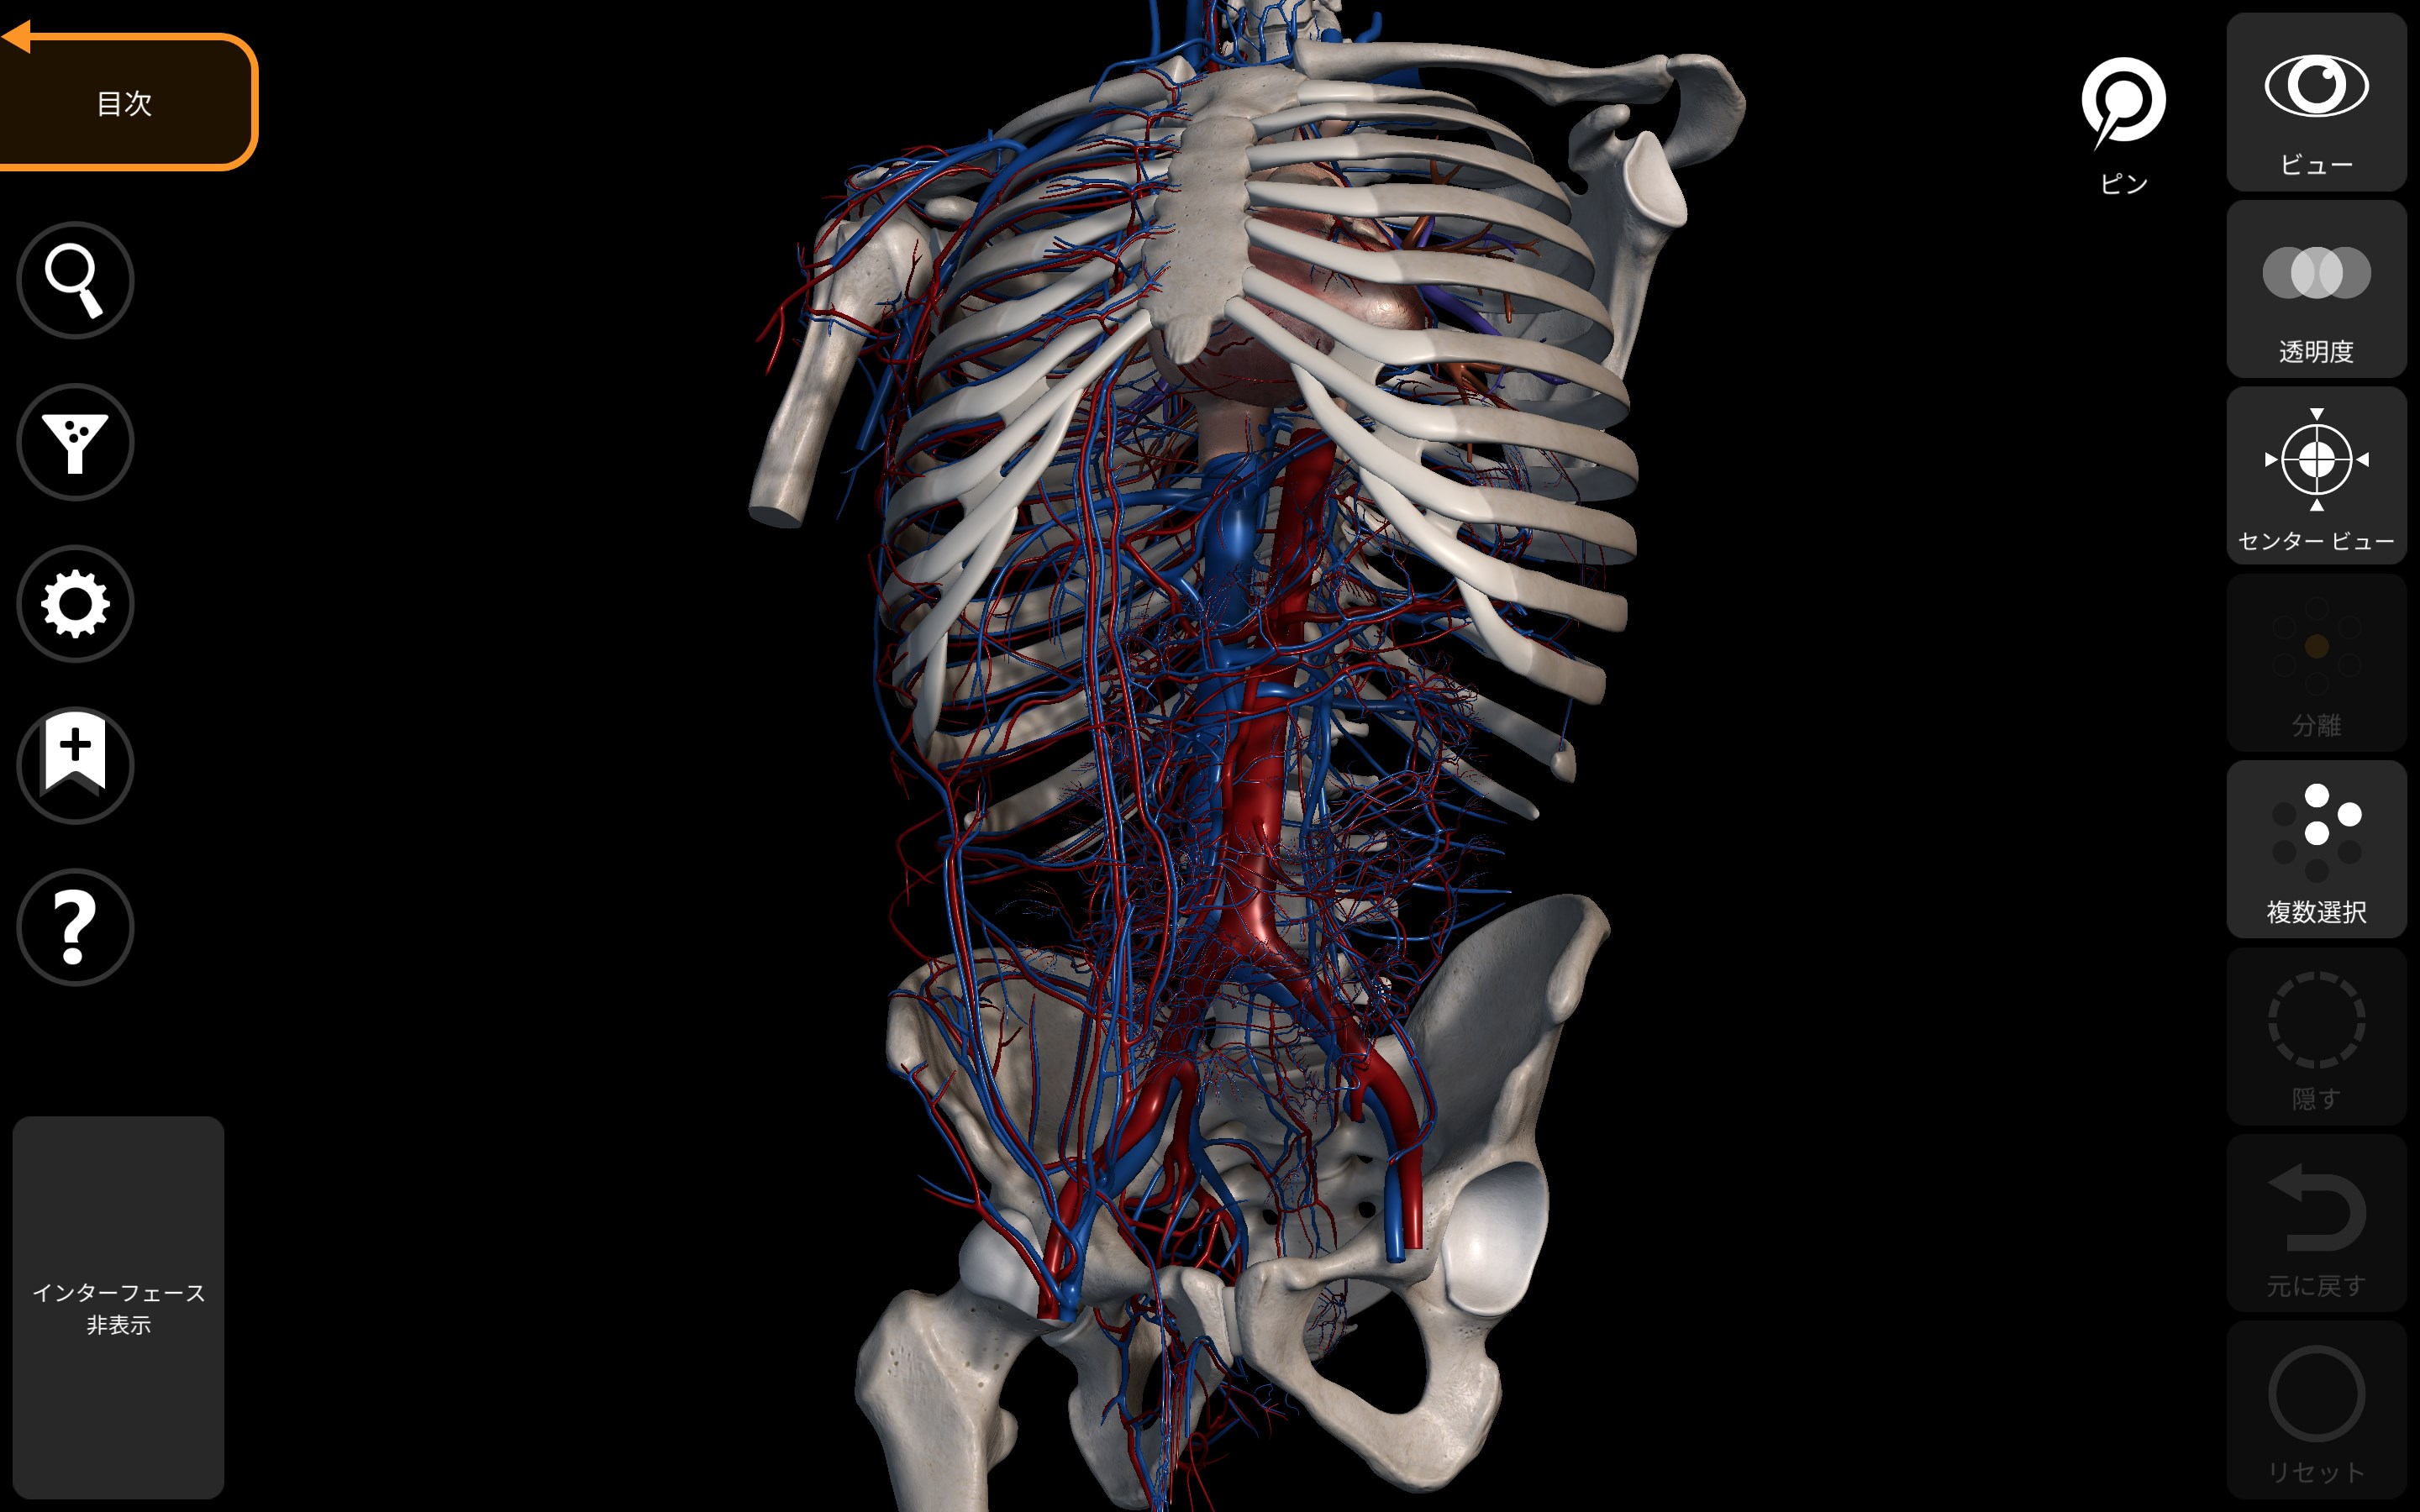

ヒト発生の3次元アトラス (3D Anatomy Project) | 塩田浩平 |本,

ヒト発生の3次元アトラス (3D Anatomy Project) | 塩田浩平 |本, ヒト発生の3次元アトラス|書籍・jmedmook|日本医事新報社,

ヒト発生の3次元アトラス|書籍・jmedmook|日本医事新報社, 解剖学 - 3Dアトラス - Anatomy 3D Atlas - Windows に無料で,

解剖学 - 3Dアトラス - Anatomy 3D Atlas - Windows に無料で, mqdefault.jpg,